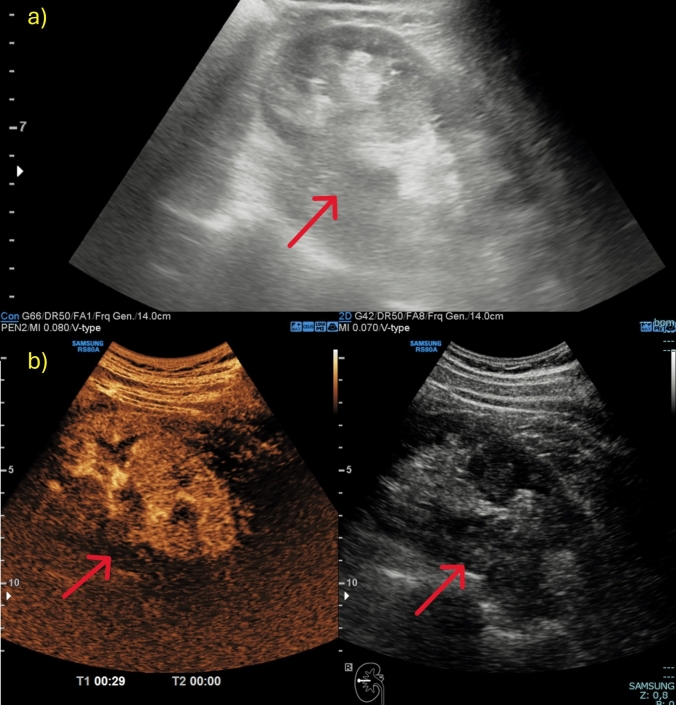

对比增强超声(CEUS)已成为检测和表征实性肾脏病变的重要工具,补充了传统的b型超声,后者往往难以区分实性和囊性肿块。超声造影通过提供详细的血管化信息来提高诊断的准确性,有助于识别潜在的恶性实体病变,并区分假肿瘤和实体肿块。此外,超声造影使用的造影剂即使对肾病患者也是安全的,并且可以不考虑肾功能,使其成为肾脏成像的有利方法。在这篇叙述性综述中,根据欧洲超声医学和生物学协会联合会的指南,作者展示了其主要适应症:在移植肾患者中诊断不确定的肾脏病变,监测非手术病变,诊断炎症-感染性肾脏病变,评估手术床上的晚期肾脏病变和肿块。

Contrast-enhanced ultrasound (CEUS) has become an important tool for the detection and characterization of solid renal lesions, complementing traditional B-mode US, which often struggles to distinguish between solid and cystic masses. CEUS enhances diagnostic accuracy by providing detailed vascularization information, helping to identify potentially malignant solid lesions and differentiate between pseudotumours and solid masses. Moreover, CEUS employs a contrast agent that is safe even for nephropathic patients and can be used without concern for kidney function, making it an advantageous method for renal imaging. In this narrative review, following the European Federation of Societies for Ultrasound in Medicine and Biology guidelines, the authors show its main indications: characterizing indeterminate renal lesions in patients with transplanted kidney, monitoring non-surgical lesions, diagnosing inflammatory-infectious renal pathologies, and assessing advanced renal lesions and masses in the surgical bed.